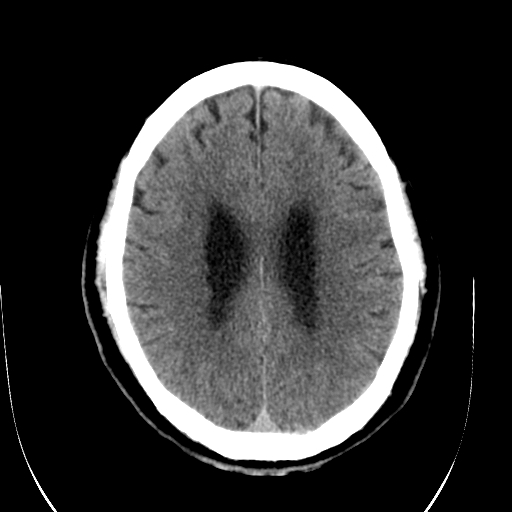

标题: CT28335:男,58岁,请各位看看是不是有脑积水,蝶窦内高密 [打印本页]

标题: CT28335:男,58岁,请各位看看是不是有脑积水,蝶窦内高密

轻度积水,蝶窦正常。

脑积水!建议行mri!

1)脑积水。2)副鼻窦炎。